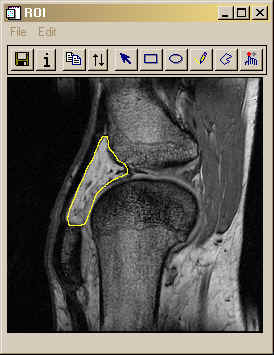

ANSWER: There are several ways to draw a free-hand line on an image, but perhaps the best way is to use the XROI tool supplied with IDL. This tool allows you to draw regions of interest (ROI) in a variety of ways. You will probably want to use the pencil tool to draw a free-hand line around your lesions. With XROI you can draw as many ROIs as you like. Notice that when you finish drawing with any of the tools the end point is connected to the start point to form a closed polygon. Each ROI is then stored in the program as an IDLanROI object. For image masking purposes, you want to recover these IDLanROI objects. You can do this with the Regions_Out keyword. Be sure, however, to make the XROI tool a blocking or modal widget. Otherwise, you won't be able to recover the ROIs outside the program. From the IDL command line, you would call the program like this:

IDL> filename = Filepath(Subdir=['examples','data'], 'mr_knee.dcm') IDL> image = Read_DICOM(filename) IDL> XROI, image, Regions_Out=thisROI, /Block

The XROI tool will look something like this after you have drawn the region of interest.

When you are finished, use the Quit button to quit the XROI tool. You can define several ROIs with the tool. If you do, the variable thisROI will be an arrary of IDLanROI objects. In this example, I am going to assume you only defined a single ROI (so I don't have to write a loop).